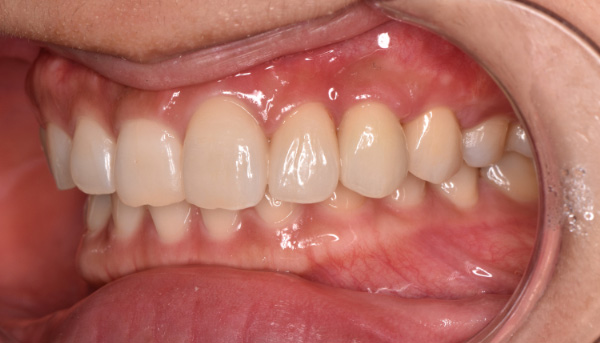

治療後

前歯のインプラントで特に審美的に要求の高い患者様でしたので、当院で最も信頼性の高いインプラント治療プランをご選択いただきました。また、前歯の左右差をコンポジットレジン(CR)修復治療で整えました。

| 主訴 | 根が折れてしまった歯をインプラントにしたい。 合わせて前歯の左右差を治したい。 |

| 治療期間 | 約4ヶ月 |

| 治療費 | 1本あたり550,000円(税別) |

| 治療内容 | 前歯のインプラント治療 |

| 治療のリスク | 前歯のインプラント治療では、審美性の問題や骨密度不足によるインプラントの不安定、神経損傷や感染のリスクがあり、術後の腫れや痛みも発生する可能性があります。 |